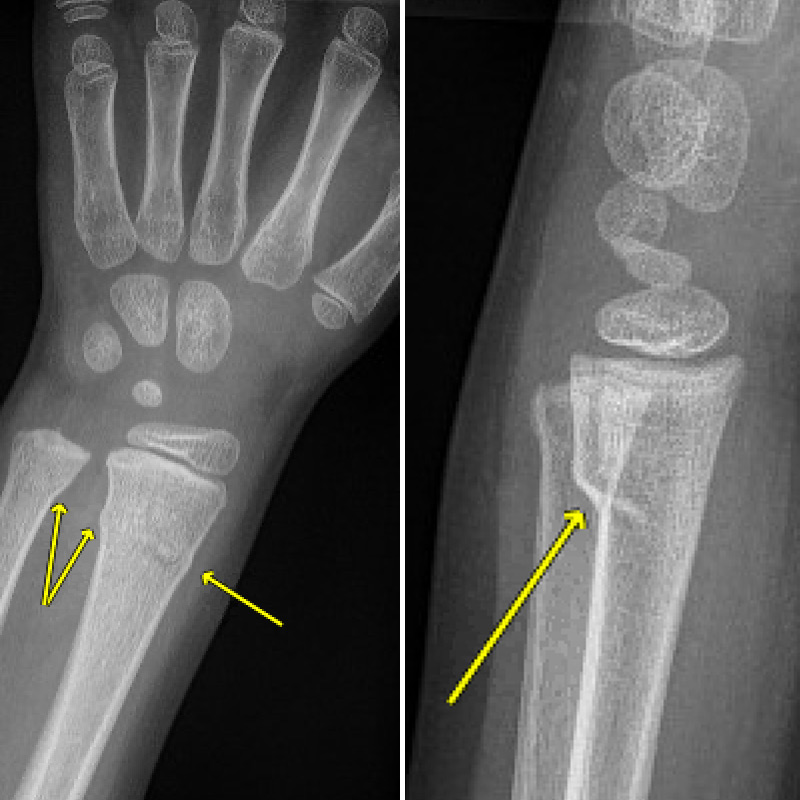

xray of the forearm of an infant showing a greenstick (buckle What Is A Buckle Fracture In Thumb Fractures of the thumb are usually associated with local bruising, swelling, pain and loss of function, with or without deformity. The thumb plays a major role in the critical functions of the hand. What is a buckle fracture? A buckle fracture is a break that does not go completely through the bone. By definition, a buckle fracture is a stable. What Is A Buckle Fracture In Thumb.